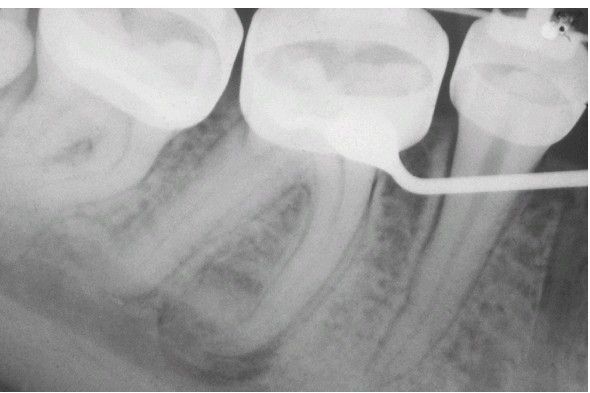

Osteoid Osteoma

. A circumscribed, mixed radiolucent and radiopaque lesion near the apex of mesial root of mandibular first molar. The patient had dull, nocturnal pain that was relieved by aspirin.